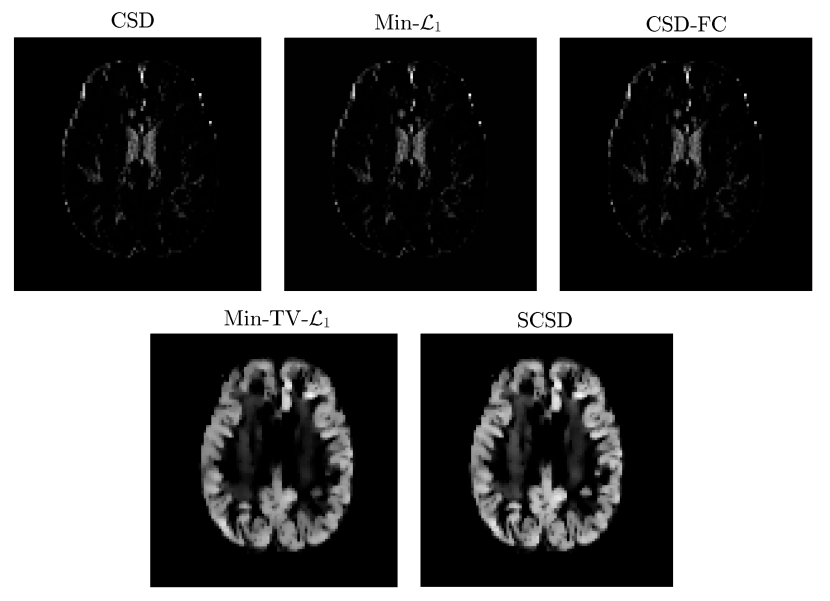

Refer to caption

Figure 8. An “axial” slice of the IDMs recovered by different SD methods under comparison for b=3000𝑏3000b=3000 s/mm2, α=45𝛼superscript45\alpha=45^{\circ}, and piso=0.5.subscript𝑝𝑖𝑠𝑜0.5p_{iso}=0.5.

The results of our final quantitative comparison are summarized in Fig. 7, which shows the values of contrast C𝐶C obtained using different SD methods under comparison for b=1000𝑏1000b=1000 s/mm2 (left column of subplots) and b=3000𝑏3000b=3000 s/mm2 (right column of subplots). Predictably enough, the best contrast is achieved by the Min-TV-1subscript1\mathcal{L}_{1} and SCSD algorithms, owing to their inherent ability to account for the presence of isotropic diffusion. Moreover, out of the two, the proposed SCSD algorithm yields the higher values of C𝐶C for all simulated scenarios. An additional illustration of the effect of incorporation and spatial regularization of the isotropic diffusion component is provided in Fig. 8, which depicts a 2-D “axial” slice of the IDMs reconstructed by different SD methods under comparison for b=3000𝑏3000b=3000 s/mm2, α=45𝛼superscript45\alpha=45^{\circ}, and piso=0.5subscript𝑝𝑖𝑠𝑜0.5p_{iso}=0.5. (Note that, for the sake of the clarity of visualization, the IDMs in Fig. 8 have been normalized so as to make their minimum and maximum values correspond to black and white pixel values, respectively.) One can see that the IDM reconstruction produced by SCSD is virtually indistinguishable from the original IDM (as shown in the upper, leftmost subplot of the figure), with the second best result produced by the Min-TV-1subscript1\mathcal{L}_{1} algorithm. At the same time, neither CSD, Min-1subscript1\mathcal{L}_{1} nor CSD-FC can attain a comparable accuracy of estimation of the spatial pattern of isotropic diffusion, as represented by the original IDM. In particular, even though their respective reconstructions do bear some global resemblance to the original IDM, the level of estimation errors is too high to deem these reconstructions useful.